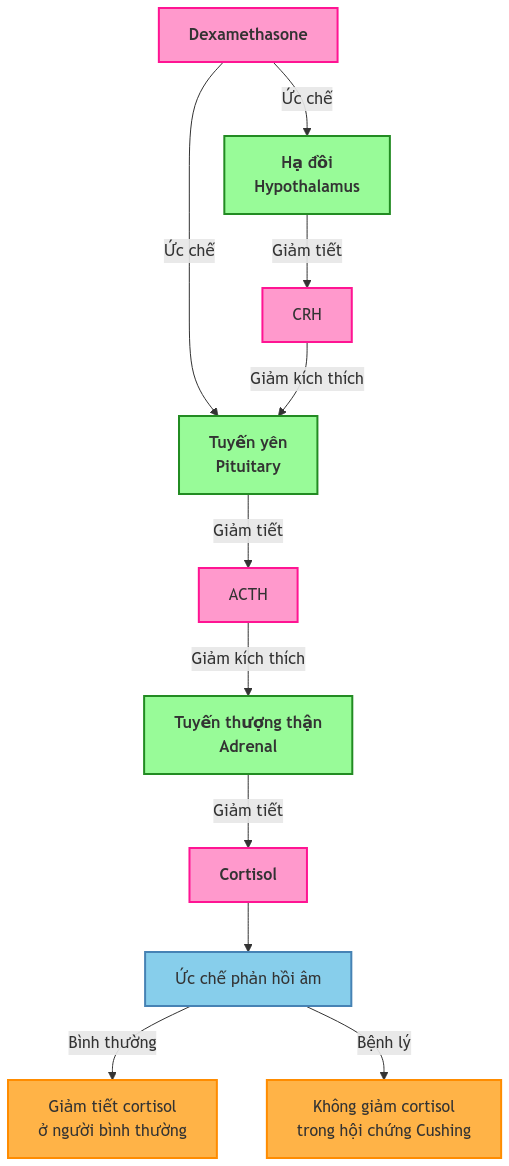

Nghiệm pháp ức chế Dexamethasone: Nguyên lý và ứng dụng lâm sàng Ths.Bs. Lê Đình Sáng, Khoa Nội tiết MỤC TIÊU: Sau khi hoàn thành bài học này, học viên có khả năng: Trình bày đầy đủ và chính xác về cơ sở sinh lý bệnh, nguyên lý và quy trình kỹ thuật của nghiệm […]